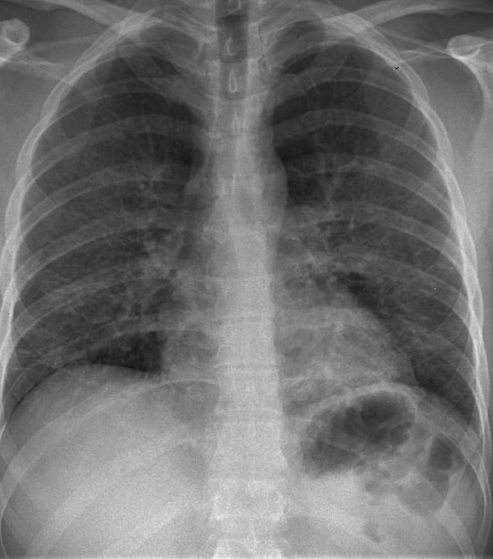

Figure 6 presents image examples for each class retrieved from the RYDLS-20 database. It is worth to mentioning that we have no further information concerning the CXR images with regarding the CXR machine used to take the image, as well as the origin, age and ethnicity of the people whose these images belong to.

Refer to caption

(a) Normal.

(b) COVID-19.

(c) SARS.

(d) MERS.

(e) Pneumocystis.

(f) Streptococcus.

(g) Varicella.

Figure 6: RYDLS-20 image samples.